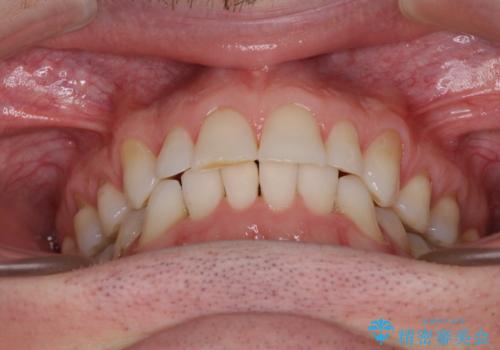

- 上下前歯の叢生を気にして来院された患者様です。

抜歯矯正をした後戻りということで、歯列不正はそれほど大きくなかったため、インビザライン・ライトを用いて矯正治療を行うこととしました。

前歯のデコボコが残っており、シミュレーション通りに動いていない部分がありましたが、再矯正であることやご本人の満足いくところまでデコボコが改善されたとのことで、治療を終了することとしました。